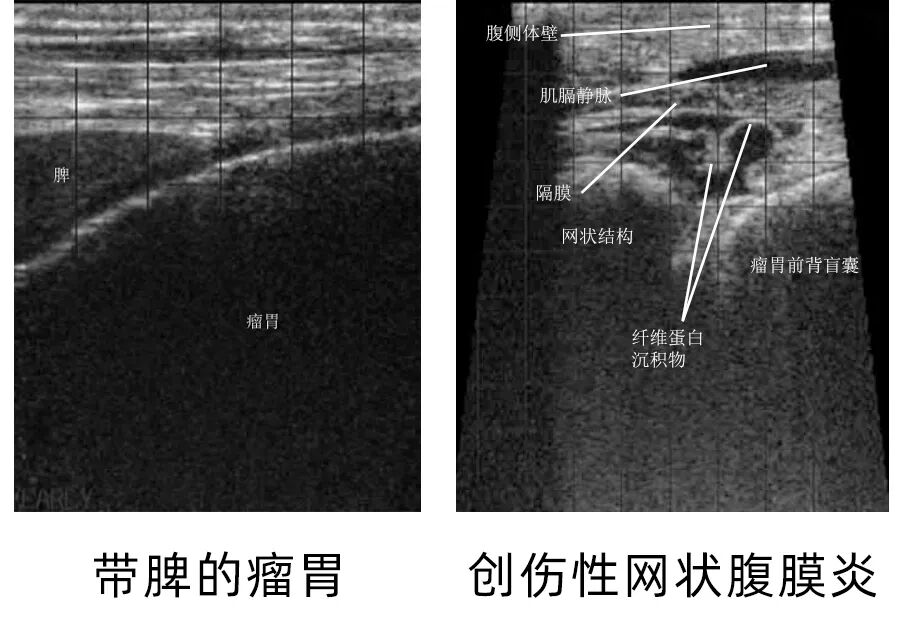

在创伤性网胃炎病例中,超声图像显示网胃运动异常,腔内液体量增多,偶尔能见到金属异物产生的强回声伴声影。左位胃变位时,胃内容物会出现在异常的区域,并表现为液气混合的回声模式。

牛用B超机测牛瘤胃